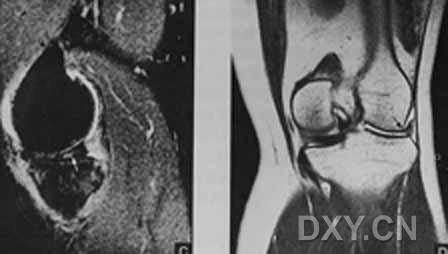

| 半月板囊肿 外侧半月板前角前缘1cm大小囊肿,合并外侧半月板前角的水平撕裂